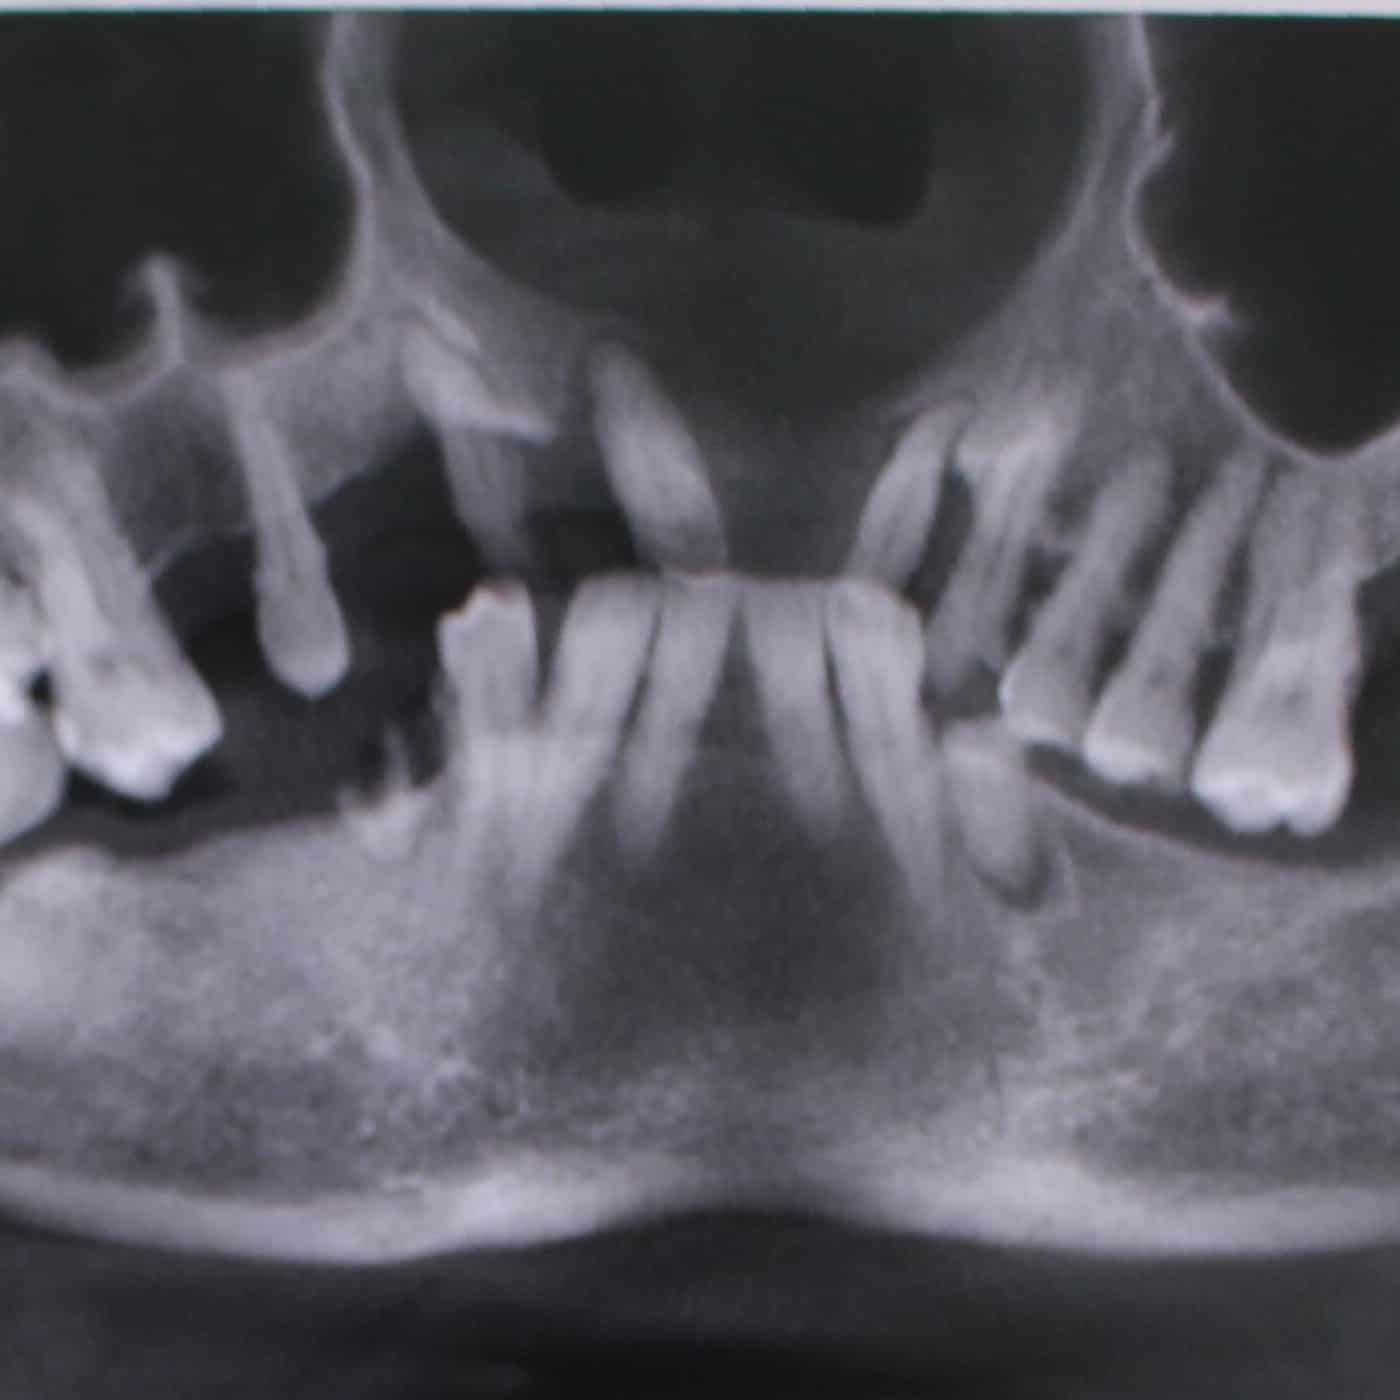

Hậu quả “mất răng mất lợi” – mất răng lâu năm làm tiêu xương hàm trầm trọng. Chụp phim 3D sẽ cho thấy tình trạng xương hàm, nướu teo lại, và cũng phát hiện các bệnh lý, tổn thương (nếu có).

Để trồng răng Implant hiệu quả, bệnh nhân cần được thăm khám và chụp CT 3D để xác định mức độ tiêu xương hàm. Bác sĩ sẽ tư vấn loại Implant phù hợp với mật độ xương hàm.

Đối với những trường hợp mất răng lâu năm làm tiêu xương hàm trầm trọng, phải kết hợp cấy ghép xương nhằm tăng cường thể tích xương hàm, giúp trụ Implant đứng vững, tích hợp tốt.